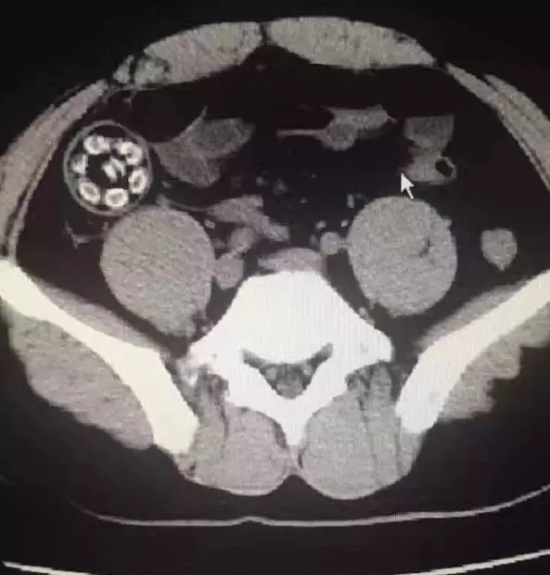

普外科医生帮林先生拍了CT后发现,他的肠道里有一颗硬物卡住,是林先生吞下的杨梅核,肠子蠕动后与杨梅核摩擦,导致肠子被割破了。检查后,林先生就转到了福州治疗。